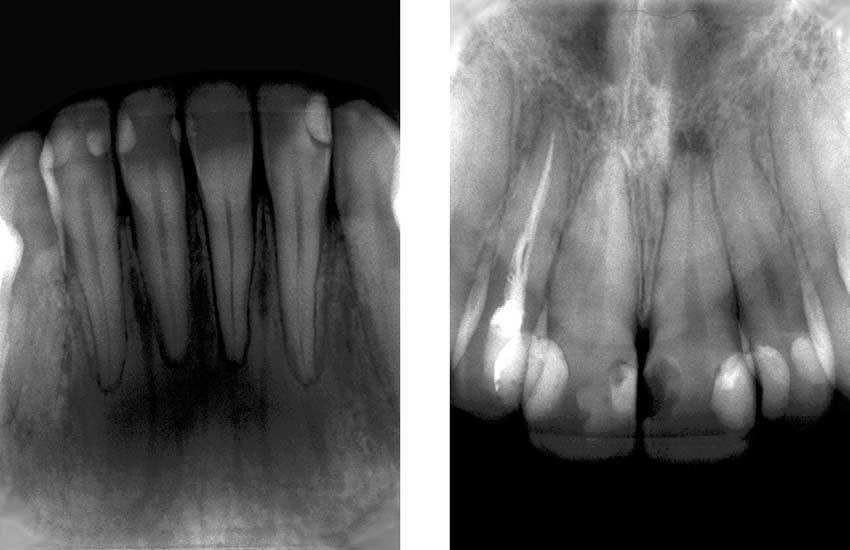

by widening the maxillary archwires and using intermaxillary elastics. When such dramatic dentoalveolar changes are observed, a main concern is periodontal support.13 For maxillary incisors, the secondary effects could include resorption of the labial cortical plate with subsequent gingival recession, dehiscence, or fenestration. With mandibular incisors, it could be lengthening of the clinical crown or resorption of the lingual cortical

plate.13 However, none of these problems was detected. Periodontal evaluation showed a healthy condition 2 years posttreatment (Fig 11). This favorable response probably occurred because the patient’s initial periodontal condition was good; attached gingivae and plaque control were adequate.25 Periodontally compromised patients might not have such a satisfactory result.26 Extraction of the mandibular third molars could be considered a controversial treatment decision. This procedure was undertaken to allow distal movement of the mandibular teeth to correct the A-P relationship. It

Fig 11. Two-year follow-up posttreatment periapical radiographs.